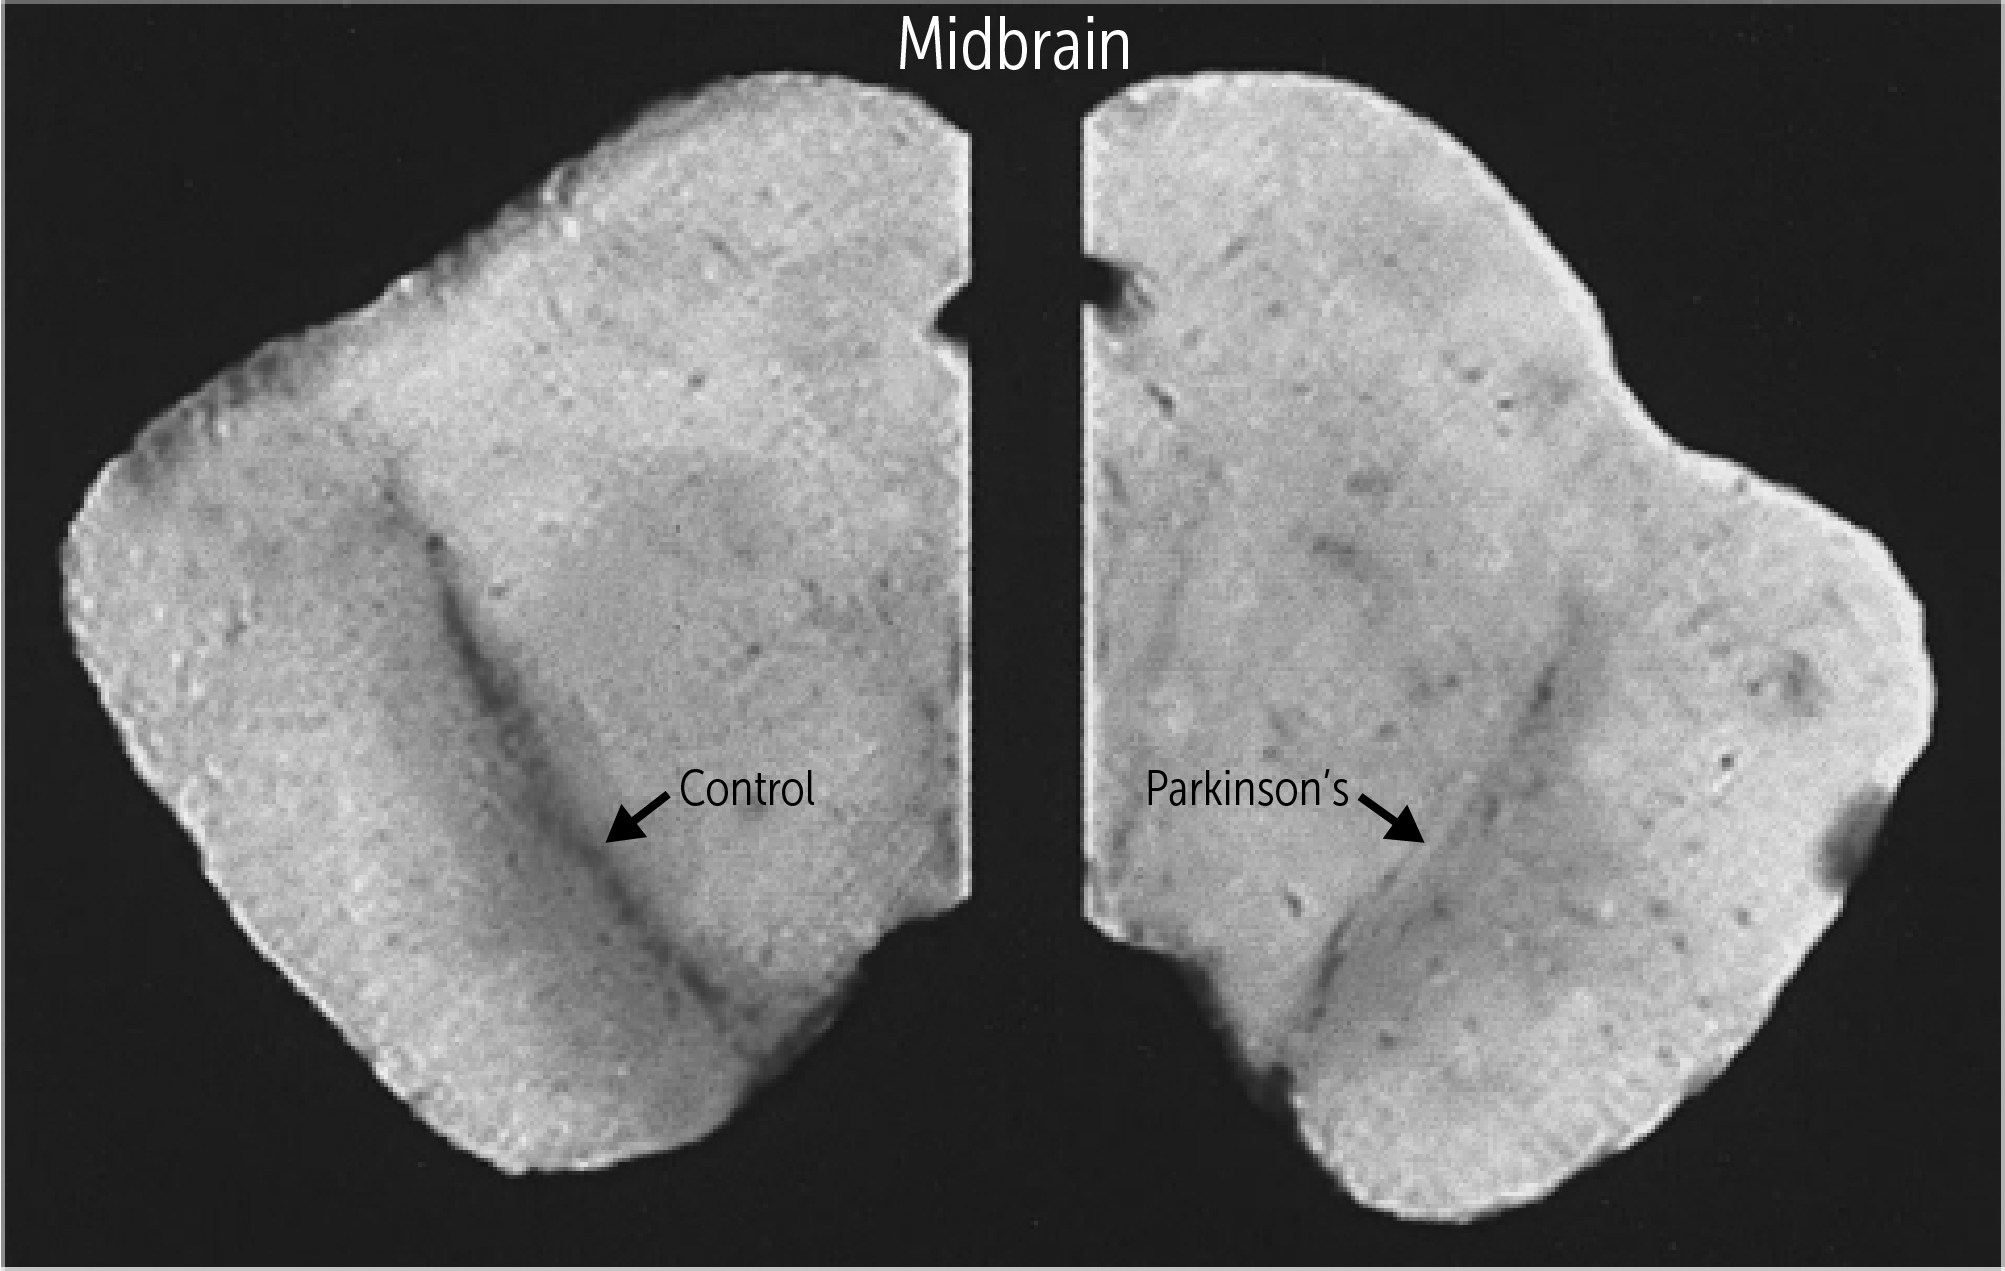

What gross change is seen on a brain cross-section in PD?

What is depigmentation of the substantia nigra?